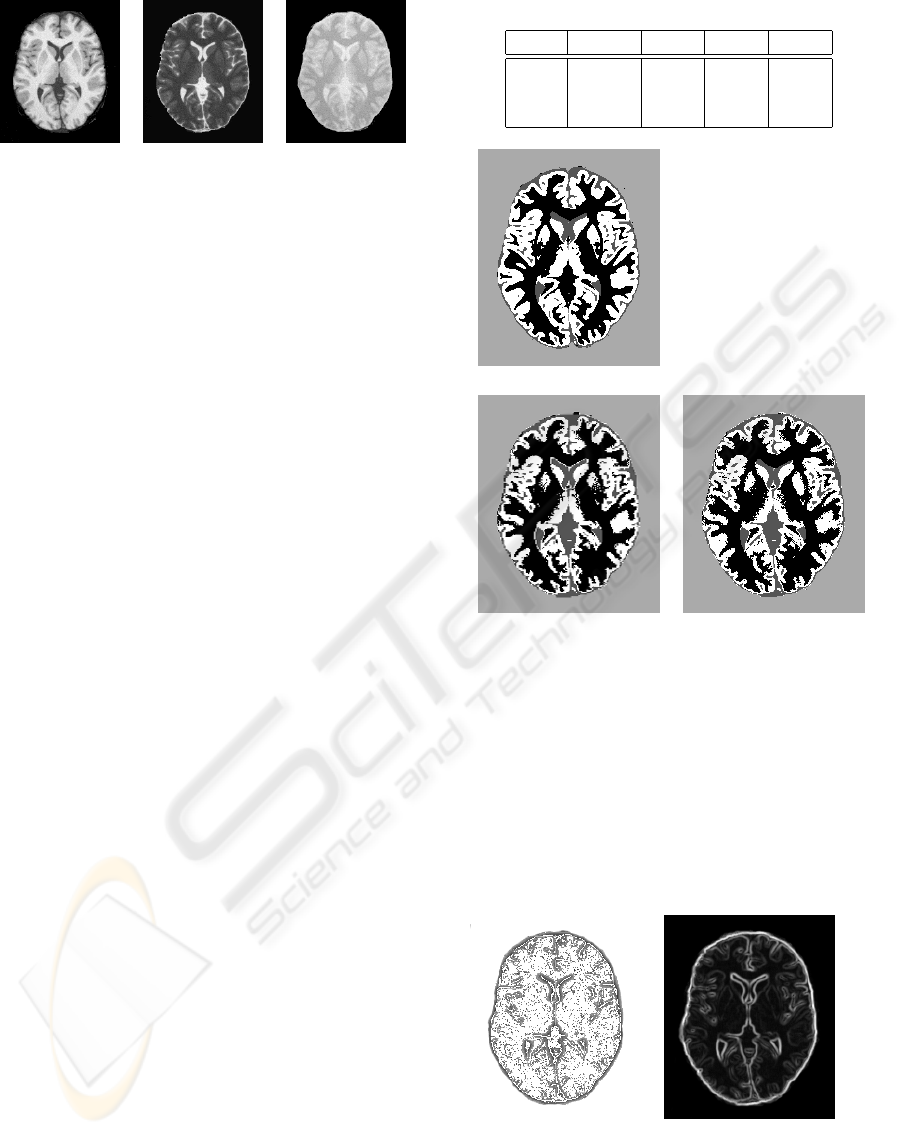

Figure 3 presents the results of the segmentation of

the brain slice in 4 classes: background (BG, light

gray), Cerebrospinal fluid (CSF, dark gray), white

matter (WM, black) and gray matter (GM, white). S1

is the segmentation obtained with only the two first

principal components, S2 with these two components

plus the LMBP and the contrast operator values.